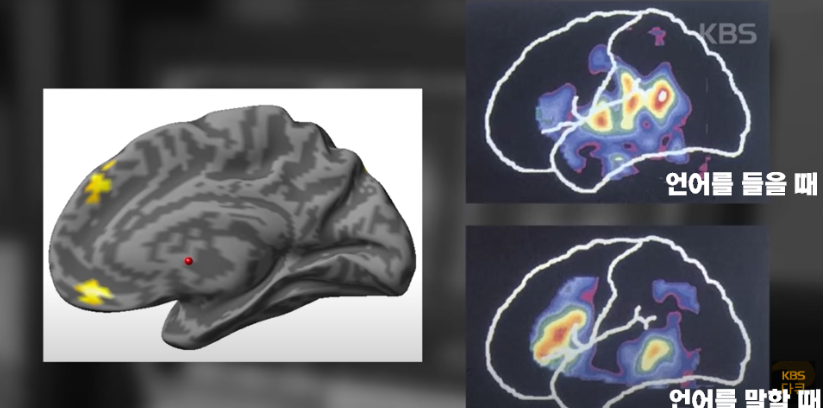

먼저, 가천의대 뇌과학 연구소와 함께 참가자들의 MRI 뇌 영상을 촬영했습니다. 참가자들은 뇌의 영상을 찍는 동안 영어 질문을 듣고 답을 생각합니다. 시험 결과, 참가자들의 뇌는 아무런 변화가 없었습니다. 모국어를 사용할 때 '언어 영역'이 활성화되는 것과는 달리, 영어를 사용할 때는 언어 영역이 특별하게 활성화되지 않았습니다.

성인의 뇌는 이미 수년간의 노출과 반복을 통해 모국어의 소리와 단어, 문법을 처리하고 생성하는 방법을 배웠기 때문에 언어 영역의 설계가 완료되었습니다. 반면 영어는 영어라는 언어를 처리하고 생성하는 방법을 완전히 배우지 못했기 때문입니다. 모국어와 외국어를 사용할 때 각각 활용하는 대뇌피질 영역에 차이가 있는 연구 결과도 있습니다.

어릴 때 2개 국어를 배운 사람은 모국어와 외국어를 쓸 때 같은 뇌의 영역을 쓰지만 나이 들어 배운 사람은 별도의 영역을 쓴다는 것입니다. 나이가 들면서 우리의 뇌는 모국어에 맞게 변화합니다. 그리고 다른 언어를 받아들이는 일을 점점 더 힘들어합니다. 그렇다면 어른이 되면 편안하게 외국어를 구사하기 힘든 걸까요?